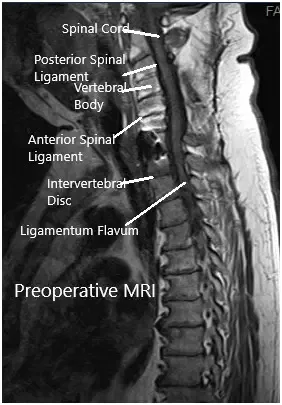

Imaging study revealed lateral disc herniations encroaching upon the neural foramen at C7-Tl and at Tl-T2, causing critical stenosis. Given his constellation of systems and weakness, we suspected also that he had a postfixed brachial plexus. obtained a thorough workup given the complexity of the patient’s imaging findings and clinical presentation and included MRI of the brain and brachial plexus.

MRI suggested postoperative changes with the fusion of the facets from C3-C7 bilaterally with laminectomies. C7-T1 vertebral bodies are fused anteriorly. There is a resultant artifact as the result of the hardware.

Mild signal abnormality in the spinal cord at C5-6 of uncertain chronicity. At T1-T2 broad-based disc bulge with articular recess narrowing bilaterally. There were lateral disc herniations encroaching upon the neural foramen at C7-Tl and at Tl-T2, causing critical stenosis.

Preoperative MRI in the sagittal section.